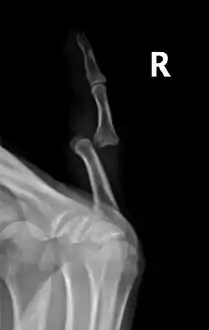

Radiograph of right fifth phalanx dislocation resulting from bicycle accident

Right fifth phalanx dislocation resulting from bicycle accident